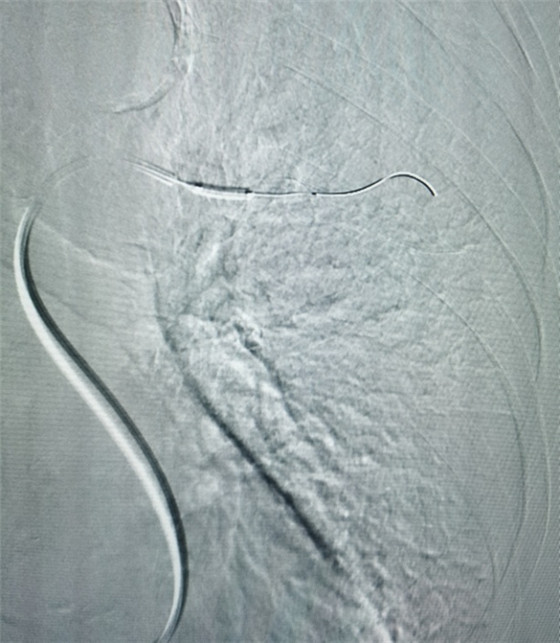

經(jīng)皮肺動脈栓塞導(dǎo)管碎栓溶栓術(shù)

經(jīng)綜合評估并與家屬充分溝通后,局麻下行肺動脈造影,提示左肺動脈主干及左肺下葉動脈閉塞,立即予以經(jīng)皮肺動脈栓塞導(dǎo)管介入碎栓溶栓術(shù)。在心內(nèi)科韋鋒主任、郭良玉主治醫(yī)師及成婷護(hù)師的默契配合下,爭分奪秒順利完成手術(shù)。術(shù)后即刻復(fù)查肺動脈造影示左肺動脈主干及左肺下葉動脈恢復(fù)血流,生命體征穩(wěn)定,指脈氧恢復(fù)至100%。經(jīng)過精心治療與護(hù)理,目前患者已康復(fù)出院。